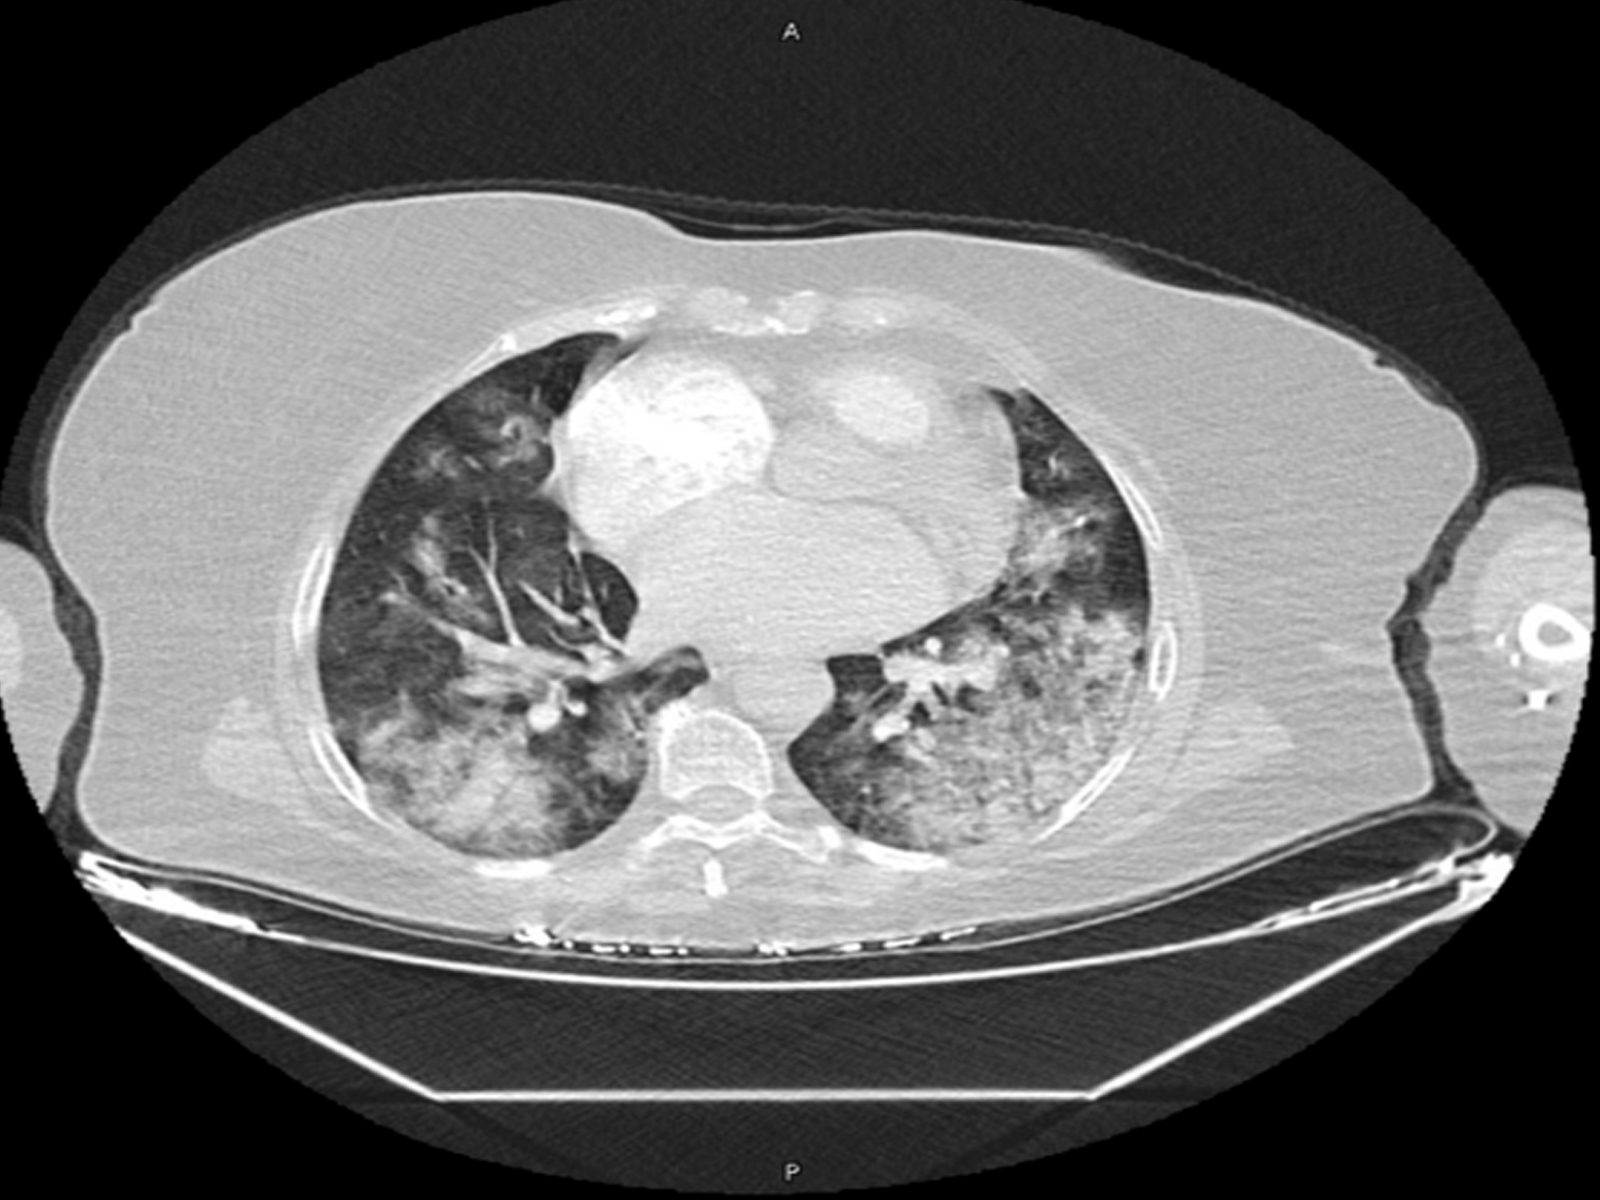

Chemotherapy-Induced Lung Disease: A Case Series

Ceren Değirmenci, Özlem Şengören Dikiş, Sabri Serhan Olcay, Hacer Aybike Toptaş Öğüt, İrem Altan, Utku Tapan, Özge Oral Tapan, Ali Alkan doi: 10.5505/respircase.2026.69376 Pages 8 - 13 |